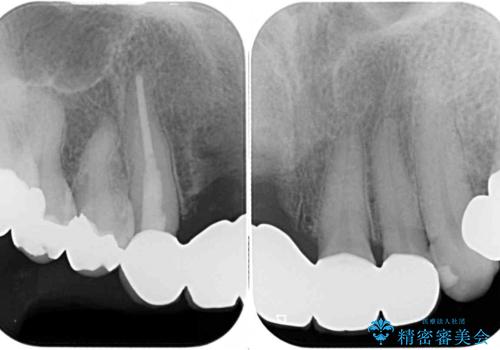

- 前歯のブリッジ治療中に装着していた仮歯が、あまりにも不自然で気になるとのことで来院された患者様です。

早急に仮歯をきれいなものに付け替え、オールセラミックブリッジにより補綴することとしました。